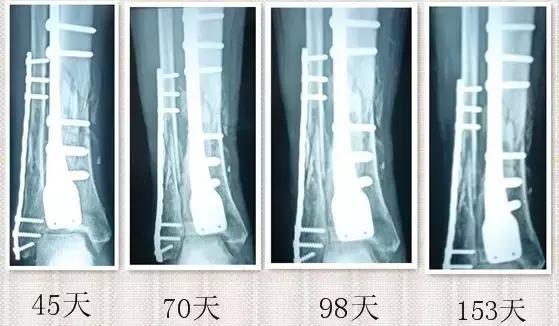

因为骨痂的生长没有感觉,所以患者最好在骨折后1个月,3个月,6个月到医院拍片检查,如果出现骨痂没有生长,骨折线清晰的状况,要连续两个月,每月检查。连续3个月骨痂没有生长,就是有骨不愈合的倾向,要及时治疗。